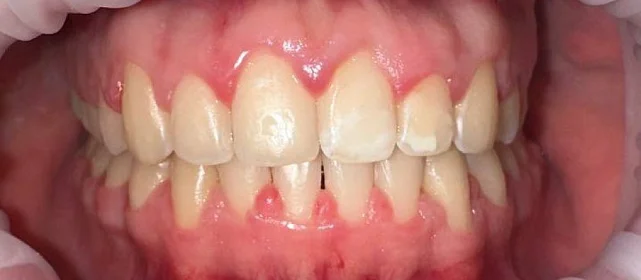

Результат

Прикус исправлен, зубы выровнены. Установлены несъёмные ретейнеры на обе челюсти, после установки коронок будут изготовлены ретенционные капы.

Решение: Установили металлические самолигирующие брекеты H4 на обе челюсти. За 28 месяцев выровняли зубы и привели прикус в норму. После снятия брекетов зафиксировали ретейнеры на обе челюсти. Пациентка направлена к ортопеду — в течение недели устанавливает коронки, после чего будет проведено сканирование и изготовлены ретенционные капы уже по окончательному контуру зубов.

Двухэтапный случай: сначала ортодонтия, потом протезирование. Ставить коронки при неправильном прикусе нельзя — нагрузка ляжет неравномерно, конструкции не прослужат долго. Брекеты H4 отработали за 28 месяцев, ряд подготовлен. Ретенционные капы сознательно делаем после коронок — контур зубов изменится, и капы должны соответствовать финальному результату.